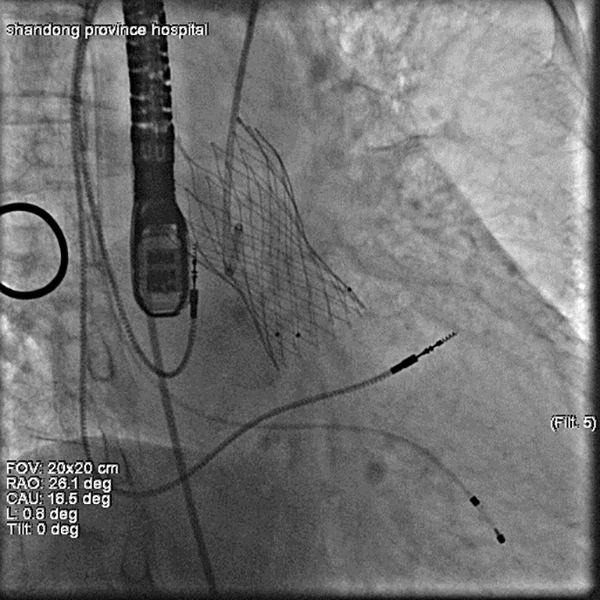

心外科王正军主任医师TAVR团队首先要为患者实施TAVR手术,患者因为急性失代偿性的心力衰竭,无法完成术前相关的CT检查,这增加术中的不确定性。面对重重挑战,在心外科团队与心脏超声科宋家光副主任医师以及麻醉手术科李伟副主任医师的配合下,顺利完成TAVR手术,随后由胃肠外科石玉龙主任医师团队对疝进行修补,术中见疝囊内有肠管嵌顿,肠管缺血坏死,将坏死肠管进行切除,行肠管切除术和肠管吻合术,随后闭合疝环,手术顺利结束。术后心脏超声提示瓣膜状态良好,狭窄解除,之后患者恢复良好后出院。

图一 术中介入瓣膜释放成功